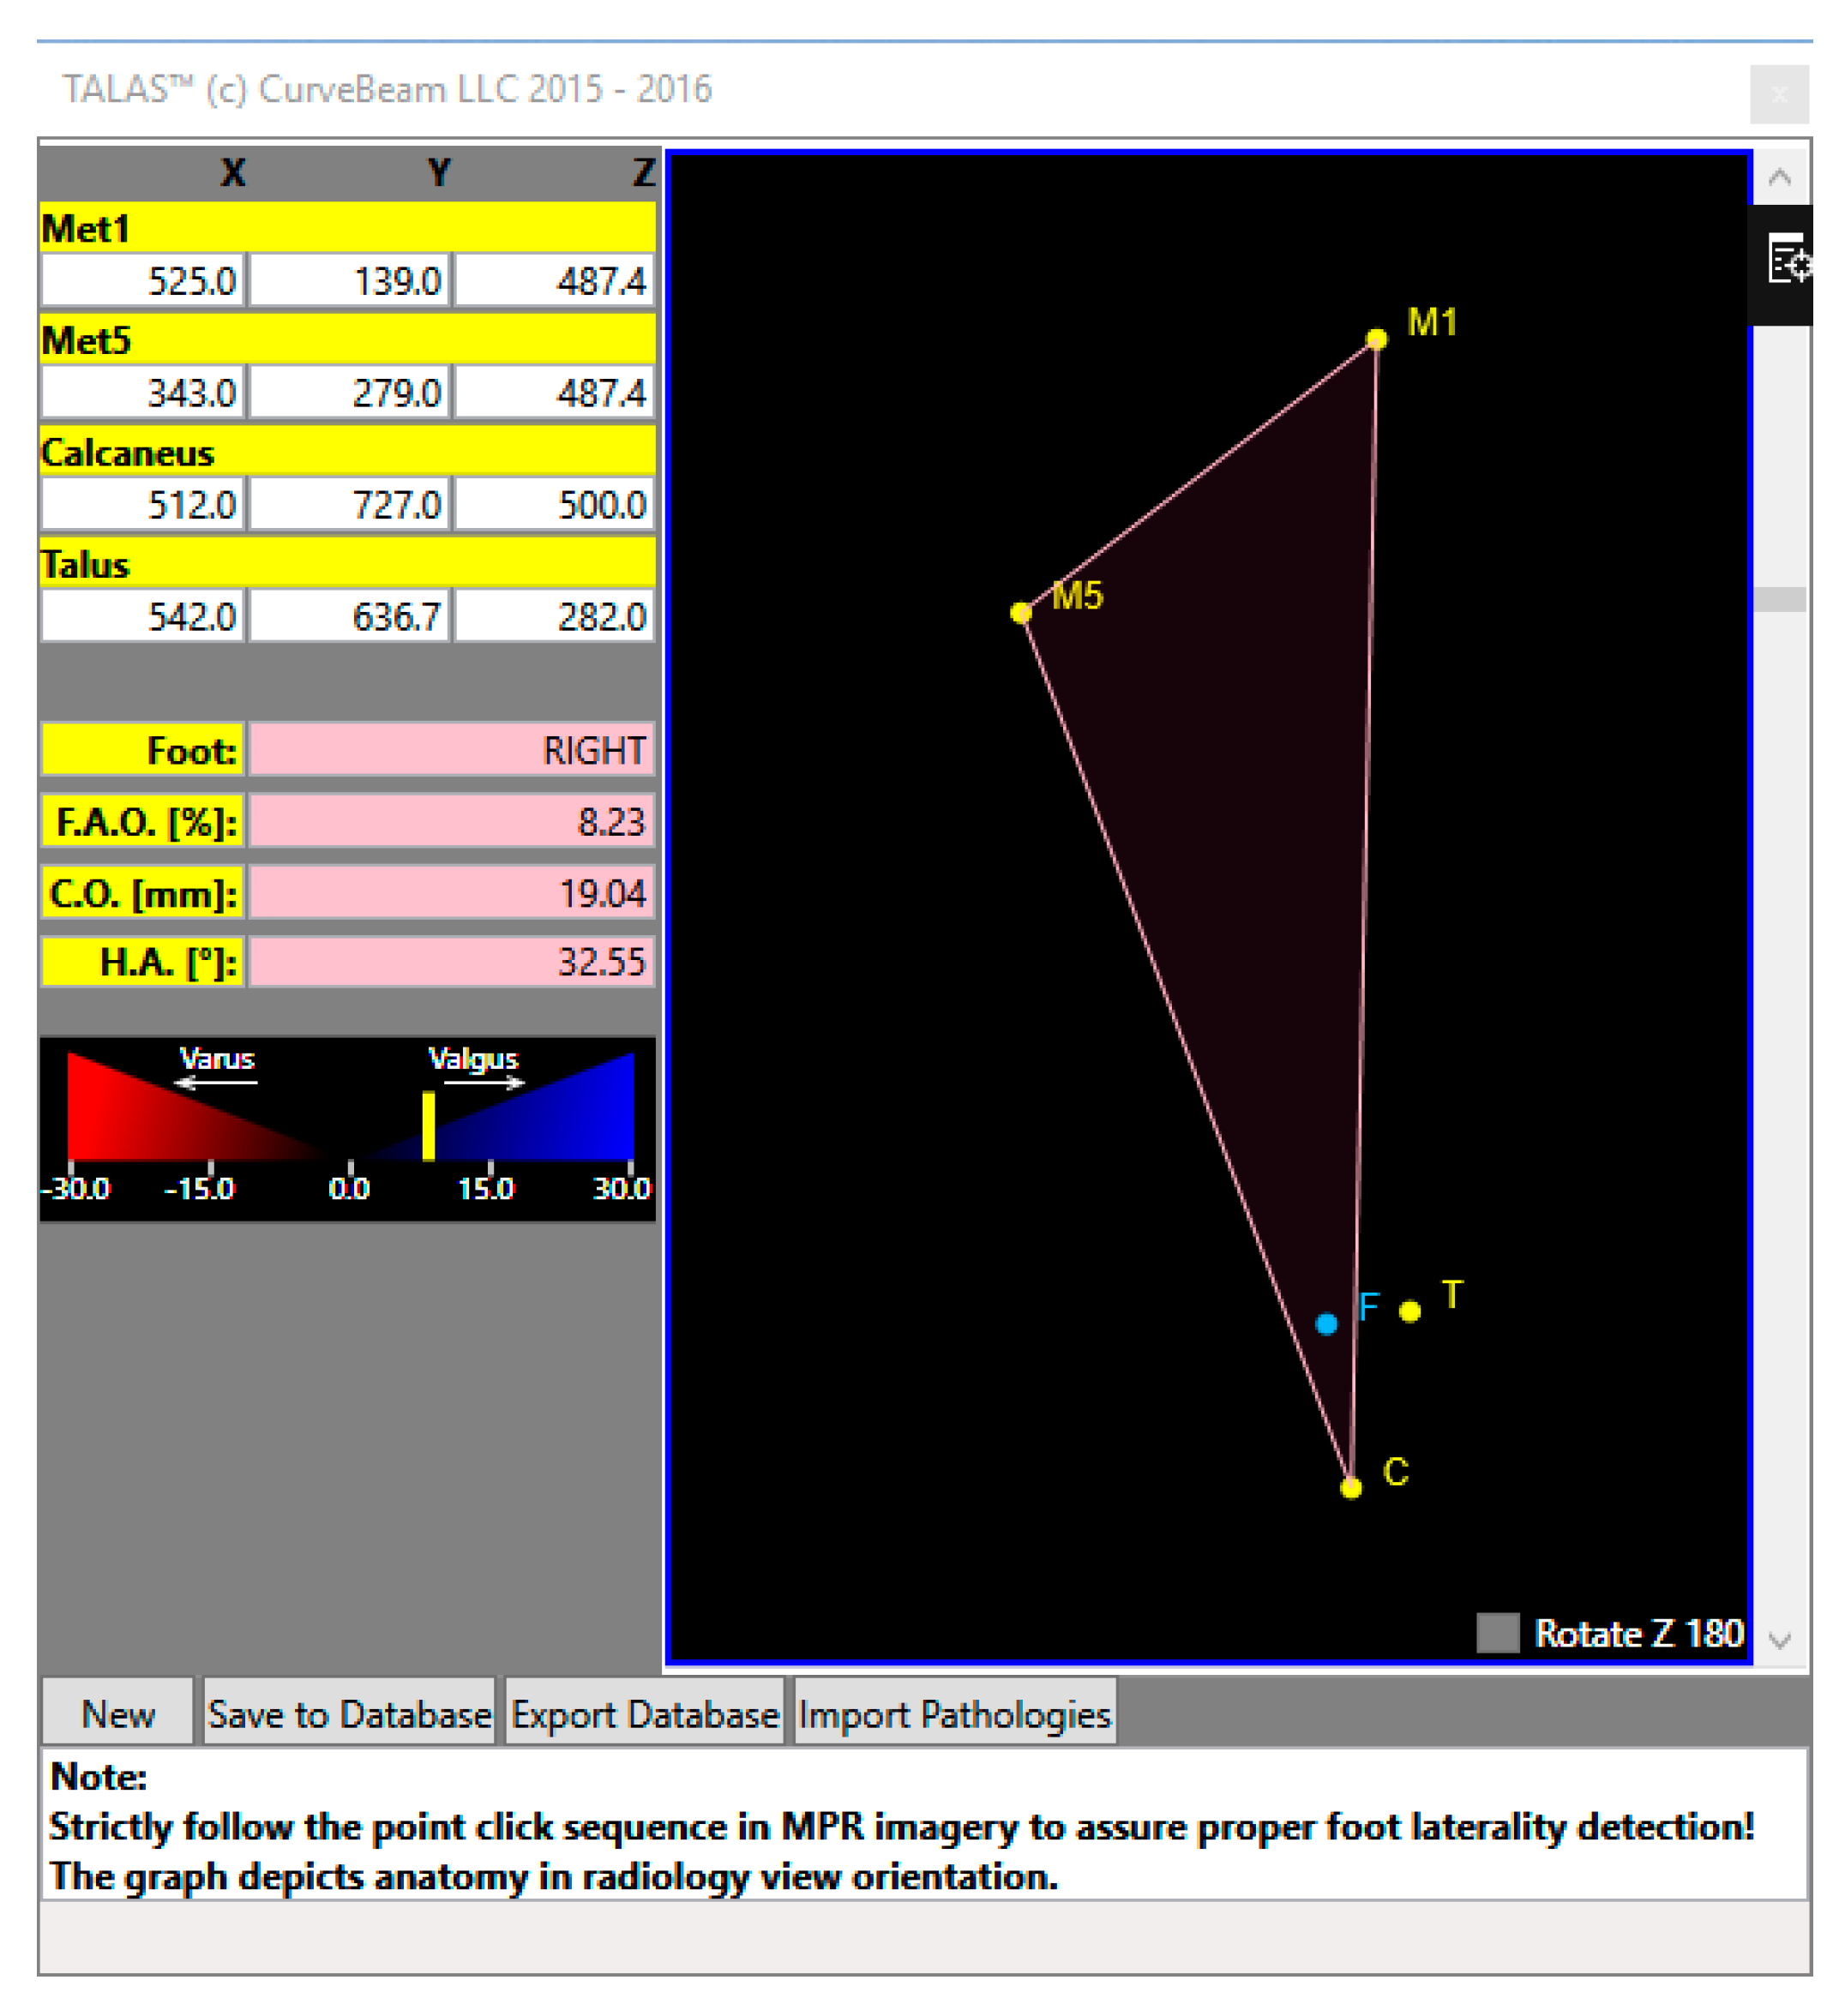

- 3D biometric techniques without segmentation

- 3D biometric techniques with segmentation (manual, semi-auto or auto)

- Semi-Automatic 3D Biometrics

- Absolute and Relative 3D Bone Measurement Reporting

- Centre of Rotation Assessment.

- Lintz, F.; Welck, M.; Bernasconi, A.; Thornton, J.; Cullen, N.P.; Singh, D.; Goldberg, A. 3D Biometrics for Hindfoot Alignment Using Weightbearing CT. Foot Ankle Int. 2017, 38, 684–689. [Google Scholar] [CrossRef]